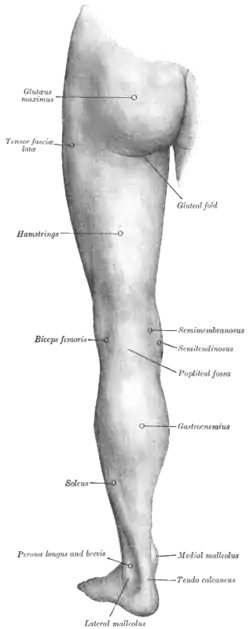

Deep nerves of the front of the leg Back of left lower extremity

Back of left lower extremity Lateral aspect of right leg